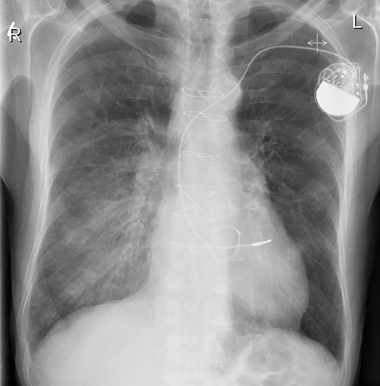

Chest x-ray at presentation showed air bronchograms at the right lower zone (Box 2). Our patient was admitted and treated for right lower lobe pneumonia with intravenous antibiotics. He was also prescribed high-dose oral steroids, with gradual tapering of doses. A computed tomography scan showed probable right lower chest infection.

During the early weeks of his hospitalisation, the patient had further episodes of acute dyspnoea, and repeat chest x-rays showed bilateral migratory opacities (Box 3). Acute episodes of dyspnoea were treated with high-dose oral steroids and intravenous antibiotics; a regular regimen of low-dose steroids was maintained between episodes. During each acute episode, his biochemistry results showed an inflammatory response, with varying elevated serum levels of C-reactive protein (CRP): 243 mg/L; 332 mg/L; 73 mg/L; 16 mg/L; 148 mg/L; and 90 mg/L (reference range [RR], < 5.0 mg/L). With treatment, the CRP level fell to 5.3 mg/L. Repeated blood and urine cultures produced no growth.